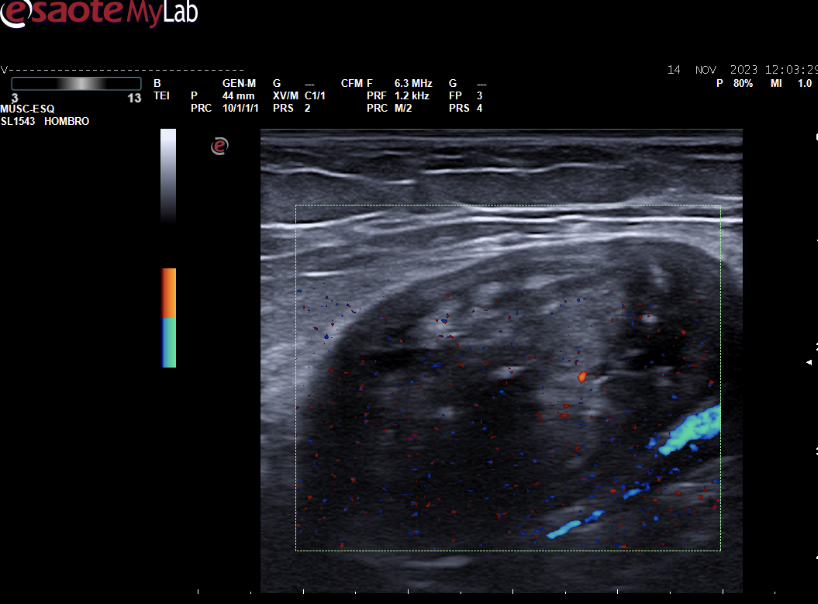

Hallazgos ecográficos

Masa heterogénea de 46*24 mm (zonas hipoecoicas con otras hiperecoicas y zona de microcalcificaciones) con escasa captación Doppler situada superficial al paquete vascular. No se observa lesión quística en la localización teórica del quiste de Baker.

se solicita ecografía reglada a Rayos.